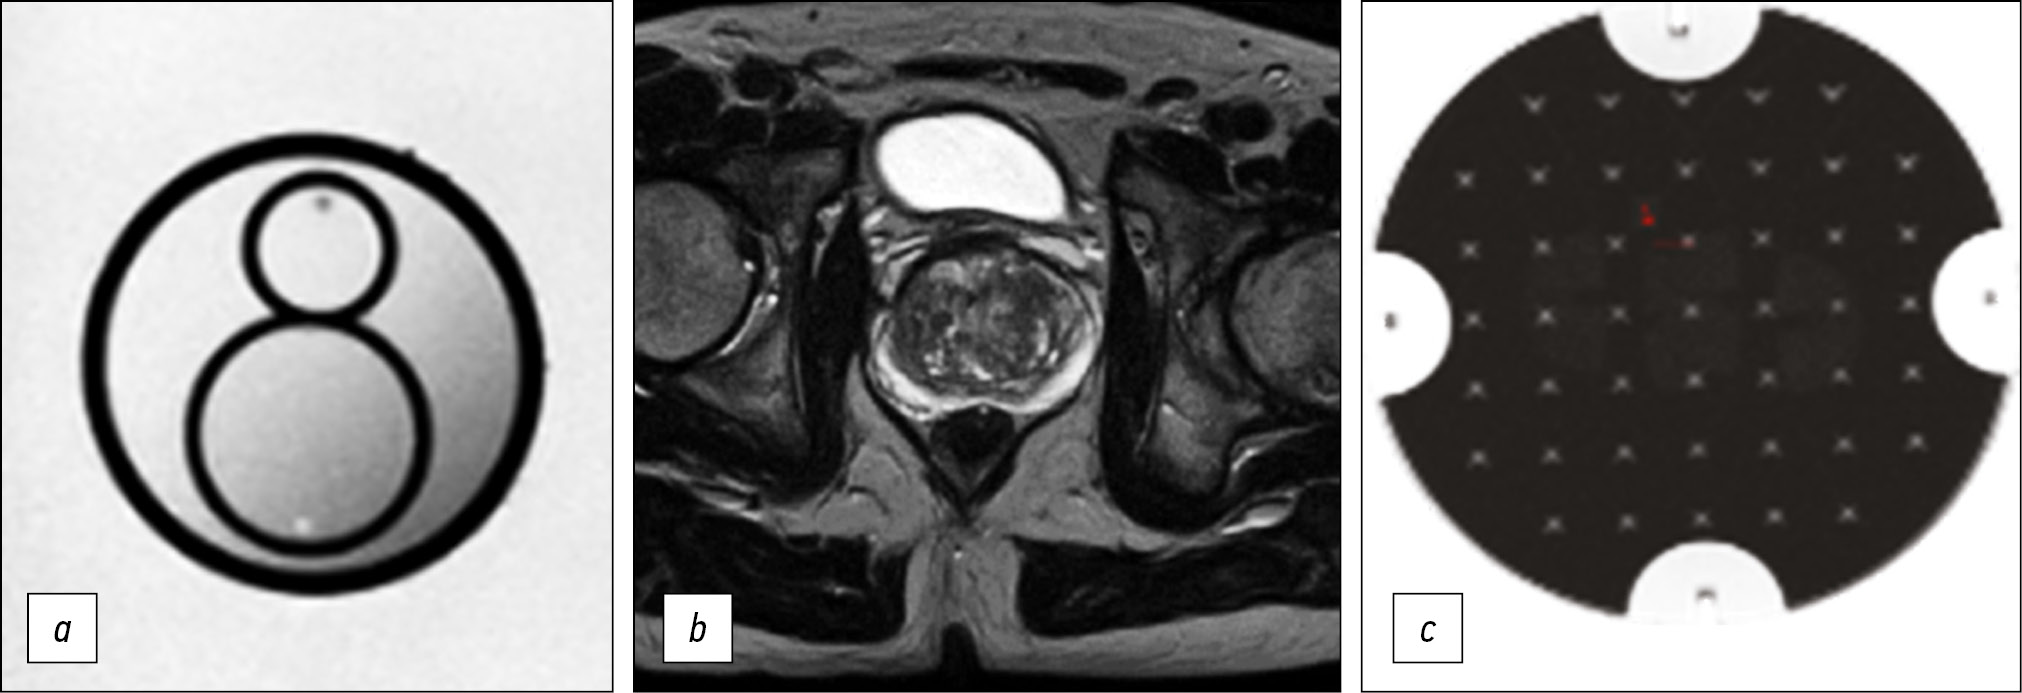

Обоснование. Рак предстательной железы занимает одну из лидирующих позиций в структуре онкологической заболеваемости среди мужчин. Актуальные на сегодняшний момент рекомендации PI-RADS формируют требования к протоколу магнитно-резонансной томографии, которые невозможно полностью реализовать на значительной части функционирующих томографов. В результате подход к выполнению исследования варьирует в разных медицинских организациях, что нередко негативно влияет на качество интерпретации изображения и диагностику целевой патологии.

Материалы и методы. Предварительный анализ полученных магнитно-резонансных изображений предстательной железы в медицинских организациях Департамента здравоохранения города Москвы показал отсутствие единого подхода к выполнению данного исследования. Методом итерационной корректировки параметров сканирования нами был настроен протокол, обеспечивающий приемлемое качество визуализации при максимально возможном соответствии требованиям PI-RADS. Для количественной оценки качества получаемых изображений применялся фантом для контроля магнитно-резонансной томографии, рекомендованный Американским обществом рентгенологов.

Результаты. Разработан оптимизированный бипараметрический протокол для томографа Excelart Vantage 1,5 Т, включающий Т2-взвешенные изображения в трёх плоскостях и диффузионно-взвешенные изображения общей длительностью менее 11 мин. При этом обеспечен высокий уровень детализации предстательной железы, а параметры качества изображения (неоднородность яркости, нелинейность, разрешающая способность и толщина выделяемого среза) соответствовали допустимым производителем диапазонам.